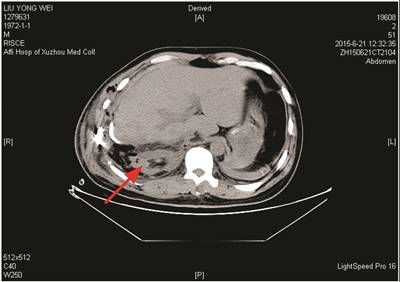

图一 2015年6月21日(术后第1天)CT,右肾如箭头所示。

2016年5月5日下午,徐州市卫生计生委组成调查组展开调查,专家组初步意见如下:患者为车祸导致的多发性骨折、肝及右肾挫伤等复合型外伤,在当地医院救治后转至徐医附院,在徐医附院术后第一天、第五天的CT检查均显示右肾存在。初步判断存在右肾损伤后血液供应障碍引起肾萎缩的可能性,需要对患者进行进一步检查。